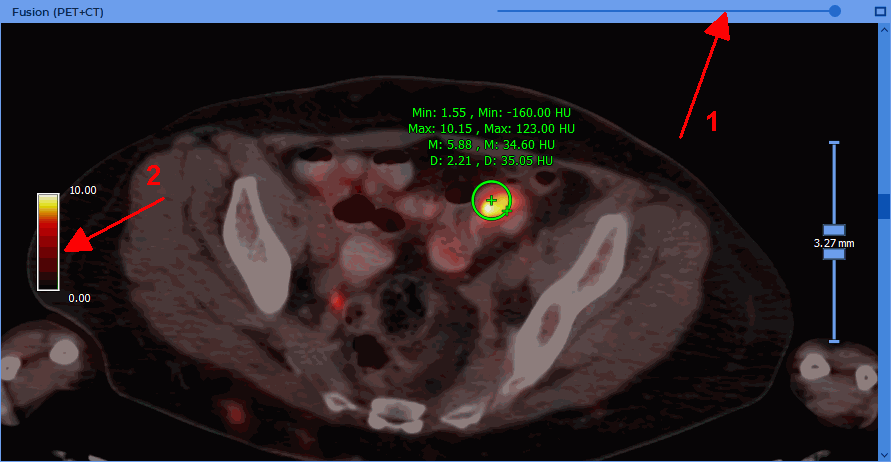

To change the PET layer opacity in the PET+CT window, move the slider at the top of the PET+CT window (marked with number "1" in Fig. 9.5).

The PET+CT window contains the scale of the CLUT for the PET layer (marked with number "2" in Fig. 9.5). If the SUV mode is disabled, the scale borders coincide with the minimum and maximum window values for the PET layer. If the SUV mode is enabled, then the scale borders coincide with the minimum and maximum values of the SUV in the current image of the PET layer.